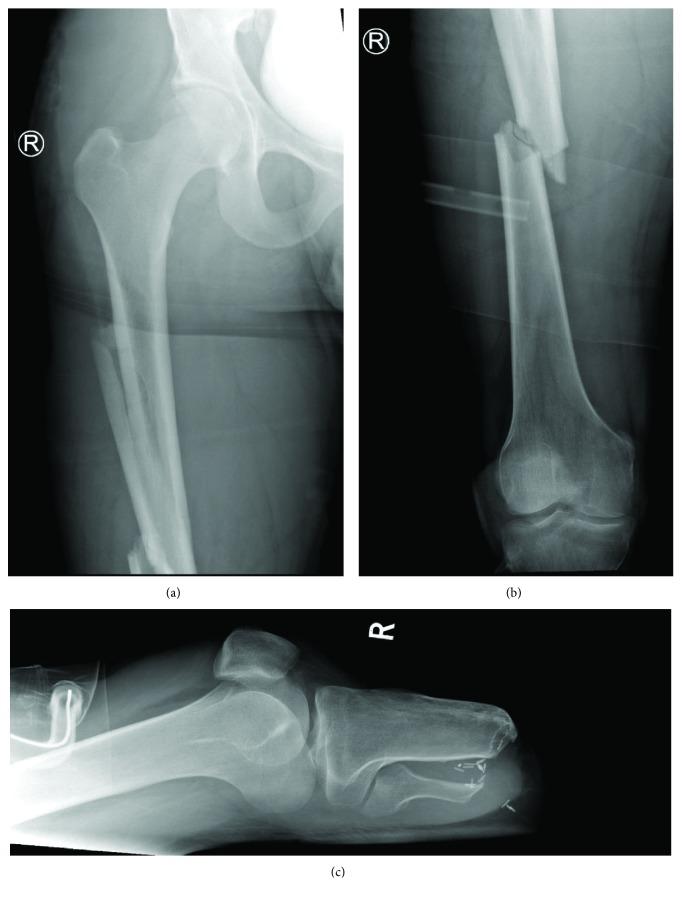

While diaphyseal femoral shaft fractures are common, it is uncommon to see this injury in leg amputees. Traditionally, these fractures are internally fixed using a fracture table with reduction obtained by traction and adequate rotation exerted on a slightly abducted extremity. Special considerations need to be given in the management of patients with leg amputations. We report the case of a 24-year-old gentleman with bilateral diaphyseal femoral shaft fractures and a previous right below-knee amputation, who was transferred to our centre following a road traffic collision. We highlight important planning that needs to be undertaken for appropriate positioning, ease of reduction, and fracture fixation. We have reviewed the literature to highlight the methods that have been previously described and our use of skeletal traction through the amputation stump that can be utilised by other surgeons in challenging situations like this.

虽然股骨干骨折很常见,但在腿部截肢患者中出现这种损伤并不常见。传统上,这些骨折通过骨折手术台进行内固定,通过牵引获得复位,并在轻度外展的肢体上施加适当的旋转。在腿部截肢患者的治疗中需要特别考虑。我们报告了一例24岁男性患者,双侧股骨干骨折,既往有右膝下截肢史,在道路交通事故后被转至我们中心。我们强调了为适当定位、便于复位和骨折固定而需要进行的重要规划。我们回顾了文献,以突出先前描述的方法,以及我们通过截肢残端进行骨牵引的方法,其他外科医生在类似这样具有挑战性的情况下也可以采用。